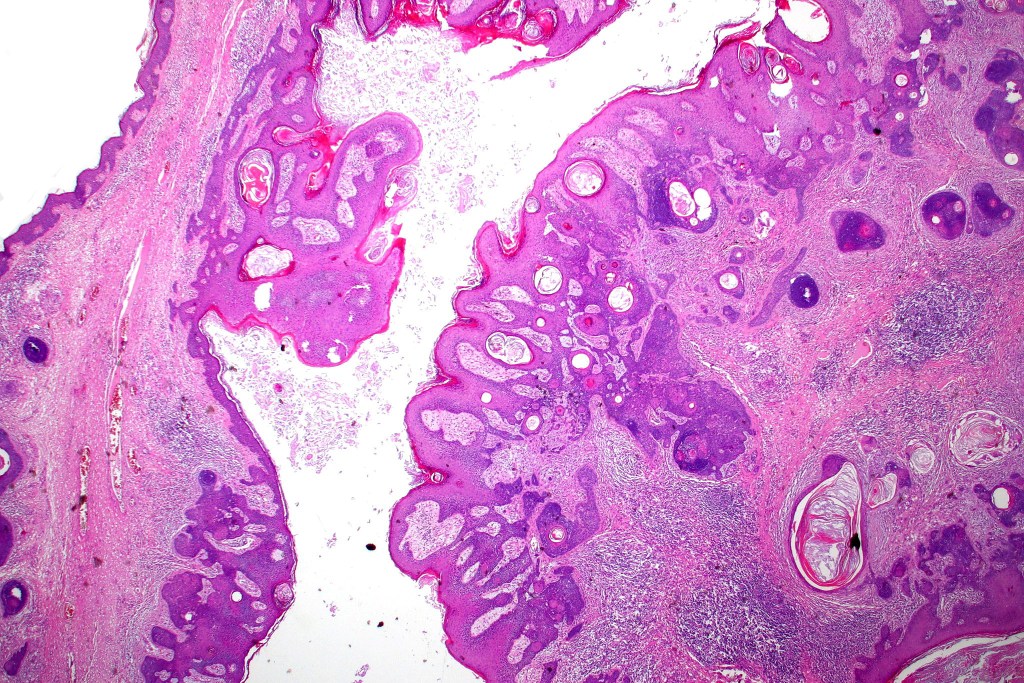

•Sharply circumscribed, unencapsulated nodule in deep dermis +/- subcutaneous fat or deeper (trichoepithelioma is much more superficial)

•Variably sized but generally large, basophilic tumor nodules composed of small uniform basaloid cells with minimal cytoplasm

•Variable keratocysts

•A rich fibromyxoid mesenchymal stroma with variable papillary mesenchymal bodies (sometimes these are absent)

•Variants include cystic, rippled pattern, pigmented, clear cell, trichoblastoma with ductal differentiation & trichoblastoma with sebaceous differentiation